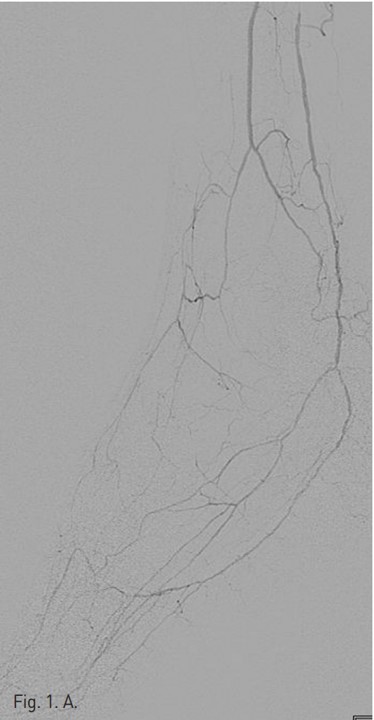

시술 당시 시행한 우측 하지 혈관조영술 (Fig. 1A)에서 right superficial femoral artery(SFA)의 mid-portion에 severe segmental stenosis가 있다. Popliteal artery는 segmental narrowing이 있고, tibio peroneal(TP) trunk 기시부에서부터 완전 폐색을 보이고 있으며, 우측 비골동맥과 후경골 동맥이 기시부에서부터 근위부 2/3 segment가 완전 폐색되어 있다(Fig. 1B).

Fig. 1. A

Fig. 1. A. An angiography of the right lower extremity shows segmental stenosis of the right superficial femoral artery.